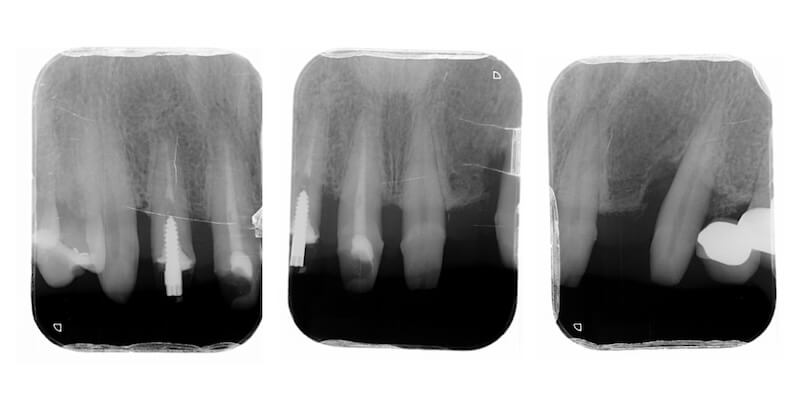

拆除舊假牙換上臨時假牙之後,開始進入牙周病的療程。我們會先將治療前口內狀況完整記錄,詳細分析每一顆牙齒的牙周狀況。

經過第一階段的療程後,我們持續追蹤 Ms.H 刷牙的情況,並且在大約兩個月後追蹤整體復原的進度,我們可以看到牙齦腫大的狀況明顯改善了許多,消腫以後產生了不少縫隙: